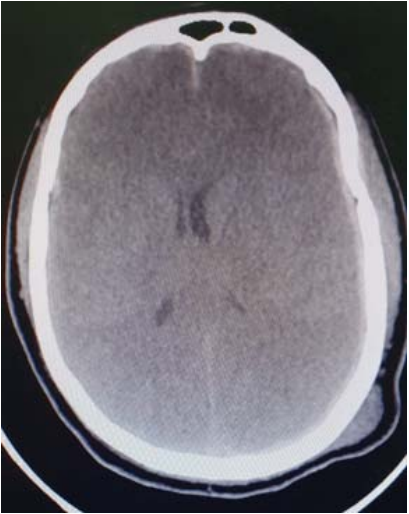

Um paciente de 31 anos de idade, com 90 kg, previamente hígido, foi trazido pelo Serviço de Atendimento Móvel de Urgência (SAMU), em imobilização padrão, após capotamento de automóvel. Relato de Glasgow 12 no momento da cena. AC = RC2T com BNF e FC = 112 bpm, AP = MVF sem RA e FR = 19 irpm, PA = 150 mmHg x 97 mmHg e SatO2 = 96%. Na avaliação inicial, apresenta abertura ocular ao estímulo doloroso com duração inferior a 10 segundos, localizando o estímulo doloroso e sons incompreensíveis, pupilas isocóricas e foto reagentes. A TC de crânio está reproduzida a seguir.

Fonte: Acervo pessoal.

Considerando esse caso clínico e com base nos conhecimentos médicos correlatos, julgue os itens a seguir.

A lesão primária, nesse caso, está associada a maior morbimortalidade quando comparado com hematomas epidurais

O paciente se encontra em Glasgow 9 e apresenta hematoma subdural agudo com desvio de linha média.